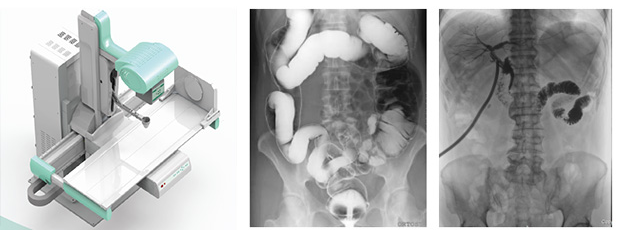

近年來,DR設備正朝著更加準確化、輕便化、智能化和多維化方向發展,出現了多功能動態DR、移動DR、三維化DR產品等等。其中多功能動態DR大大提高了普通放射設備準確診斷的能力,為臨床創造了價值。接下來給大家分析下多功能動態DR是如何提高工作效率的。以下是部分體位介紹及解決方案:

應用多功能動態DR后,在攝片中很好地解決了上述問題。因為在操作多功能動態DR檢查時,患者可取平臥位,作張口狀,球管中心線從兩口角連線的中點垂直射入,可先使用多功能動態DR的低劑量透視功能,讓病人調整好的攝片角度后進行曝光,一次即可成功。從而降低了醫生擺位要求,減少重復曝光現象。

在這些對球管中心線和受檢部位形成角度有要求的體位的擺位過程中,可以應用多功能動態DR的電動控制擺臂、數字顯示角度值和動態透視影像觀察功能等特性,使這些體位的擺位更加準確、讓醫生工作效率更高!如果您想采購普愛醫療的多功能動態DR,或了解產品技術參數,歡迎聯系我們。